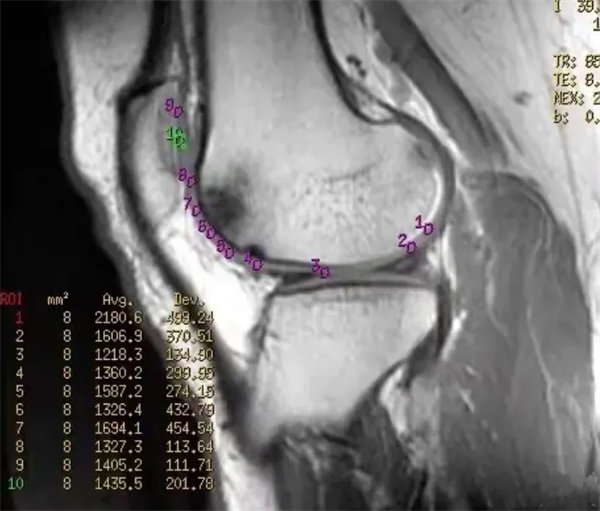

图7

原始图,损伤软骨T2mapping成像

图8

定量图,损伤软骨T2mapping成像,测相应软骨T2值。感兴趣区(ROI)3、4、7点位软骨T2值增高,分别是49ms,55ms,50ms。